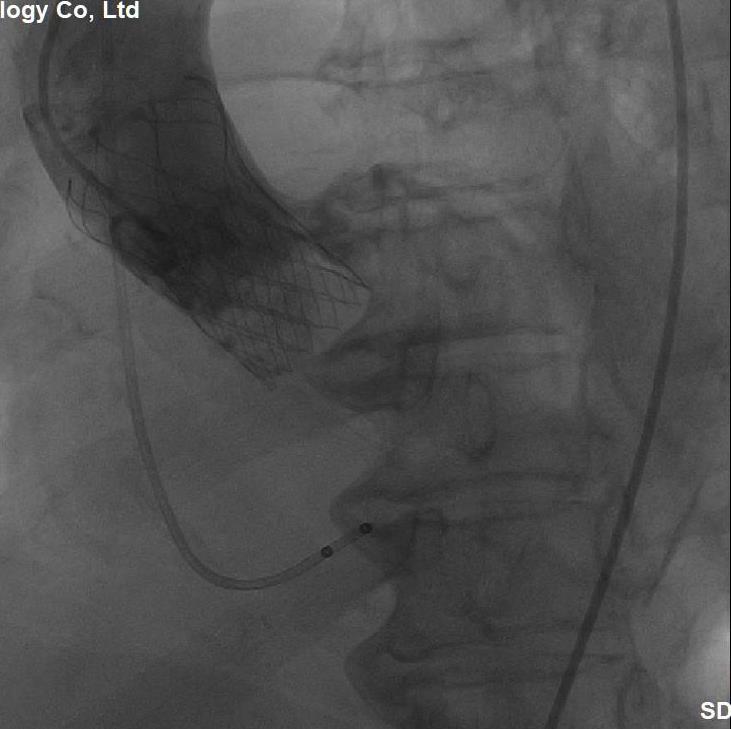

(图5,主动脉造影显示:植入的介入瓣膜位置形态满意、无瓣周分流)

(图6,多体位透视显示:介入主动脉瓣膜的位置和形态满意)

经过充分细致地准备,多学科积极协作,在张希全主任指导下,心血管外科谷兴华主任医师、急诊心内科李传保主任医师、心血管外科孙厚荣副主任医师及团队成员在绿帽社复合手术室实施手术。根据患者的病情特点,术中做好各种应急预案,备好体外循环,维持血流动力学平稳。根据术前CT分析和术中主动脉根部造影情况(图1、图2、图3),选择最佳投照体位。先选用22mm球囊,临时起搏180次/分,扩张重度狭窄的主动脉瓣(图4)。再选用24mm的介入主动脉瓣膜,造影、定位、临时起搏、顺序释放介入瓣膜,造影及心脏超声检查示:人工瓣膜位置形态满意,瓣膜启闭功能正常,主动脉瓣无瓣周分流,跨瓣压差降至8mmHg(图5、图6)。术后1小时,麻醉清醒,术后8小时顺利脱机拔管,术后第2天转入普通病房,病情稳定,治愈出院。